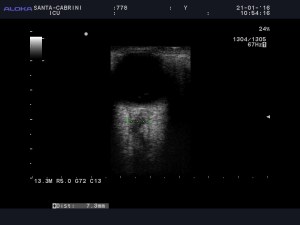

So of course we had to pick up the probe and take a look:

So the optic nerves are dilated significantly (bilaterally), suggesting an ICP over 20 mmhm at the very least.